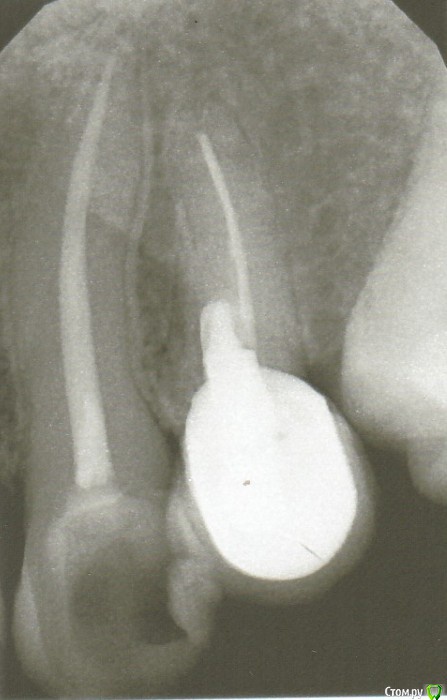

Kraas Опубликовано 31 июля, 2019 Поделиться Опубликовано 31 июля, 2019 Уважаемые врачи!4ый искусственный зуб слева сверху. От самого зуба ничего не осталось, а на том что внутри десны поставлен искусственный зуб на вкладке. Канал делался в 1995 году и переделывался в 2001 году. Возникли периодические ночные боли в области этого зуба. Снимок прилагается. Врач предлагает подождать, посмотреть что будет дальше, считает что нет ясности в причине, и что сняв зуб после лечения его не получится поставить обратно. Прислушаюсь к мнениям специалистов, сам не очень понимаю куда двигаться (а возможно никуда не надо двигаться и пить найз). Спасибо всем откликнувшимся на мой вопрос! Ссылка на комментарий

Kraas Опубликовано 31 июля, 2019 Автор Поделиться Опубликовано 31 июля, 2019 Сказать на все 100 что болит именно этот зуб я не могу, тк при постукивании или жевании этим зубом боли нет. Но когда начинается боль в ночное время, то ощущение что болит в челюсти в районе этого зуба. Ссылка на комментарий